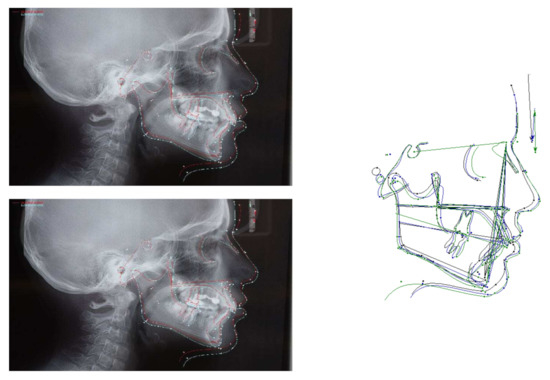

Figure 3.

Pretreatment radiographs and cephalometric analysis.

A 11-year-old patient presented to the private practice with her parents with a chief complaint of an unattractive smile, mainly due to an upper canine. The facial analysis showed an hypodivergent facial type with a reduced lower-third of the face, a convex profile with mandibular retrusion and upper lip protrusion with a proper nasolabial angle (Figure 1). The mini-esthetic analysis showed a superior inter-incisive line not coinciding with the median of the face, migrated on the left side, a ratio between arch amplitude and amplitude of the smile in the norm, and a reduced exposure of the smile with an irregular and asymmetrical smile arc. The intraoral clinical analysis revealed sagittal relationships of molar class II and canine class II, an upper interincisive line migrated on the left side, decreased transversal development of the upper arch, a severe crowding in the upper arch with a lack of space for 1.3 alignment, a 6.5 mm overjet, a 3.5 mm overbite, and an increased Spee curve (Figure 1 and Figure 2). The patient asked for treatment because the upper right canine (UR3) was not aligned and ectopic in the upper arch. Panoramic radiography and lateral cephalogram were required to confirm the diagnostic hypothesis of class II malocclusion and to measure incisors proclination. The cephalometric analysis showed a skeletal class II, hypodivergence and proclination of the upper and lower incisors (Figure 3, Table 1 and Table 2).